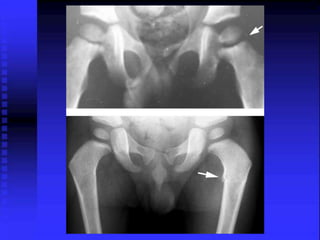

* Slight widening of the left hip joint

* Decrease epiphyseal hight

= The F.H smaller denser on the left

= Joint widening can also be 2ry to

* Slight wideningof the left hip joint * Small joint effusion R

• 64.

R = TheF.H smaller denser on the left = Joint widening can also be 2ry to hypertrophy of the cartilage.